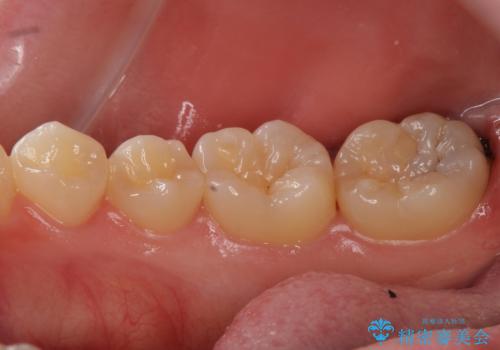

虫歯治療後、精度の良いゴールドアンレーへ

- 検査の結果虫歯が見つかった患者様です。

親知らずを抜歯してから虫歯を除去した後、ゴールドの詰め物で修復します。

比較的大きな虫歯でしたがゴールドでの修復にすることで歯の削る量を抑え、精度の高い治療を行うことができました。

親知らずの問題も同時に解決することで今後の虫歯リスクを抑えています。